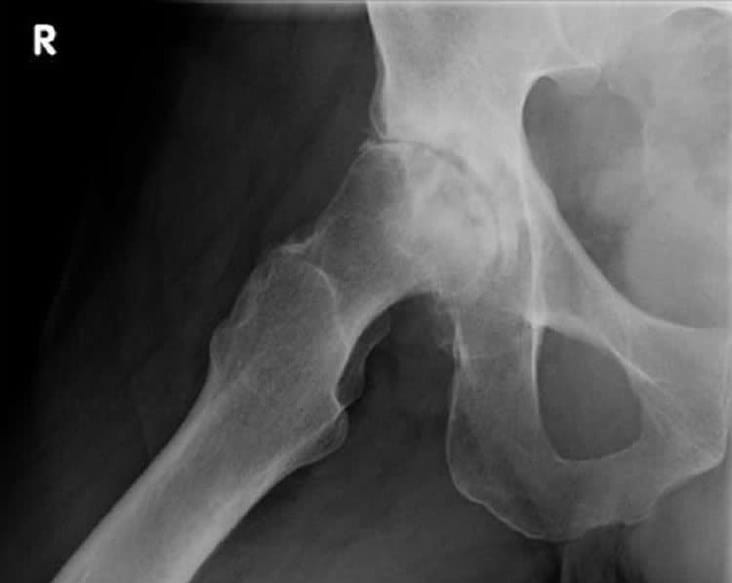

Coxarthrose (deutsch: Koxarthrose oder Hüftarthrose) ist eine degenerative, nicht-entzündliche Gelenkerkrankung der Hüfte: Die Knorpelschicht zwischen Hüftkopf und Hüftpfanne nutzt sich langsam fortschreitend ab. Wenn der Gelenkknorpel schließlich dünner wird, drohen die knöchernen Gelenkflächen aufeinanderzureiben.. Den Verschleiß des Hüftgelenkes bezeichnet der Mediziner als Coxarthrose. Diese kann sowohl unter Belastung, aber auch im Ruhezustand zu starken Schmerzen führen. Ferner kann die Beweglichkeit des Gelenks deutlich eingeschränkt sein. Woran erkennt man eine mögliche Hüftgelenksarthrose? Wann ist eine Operation sinnvoll?